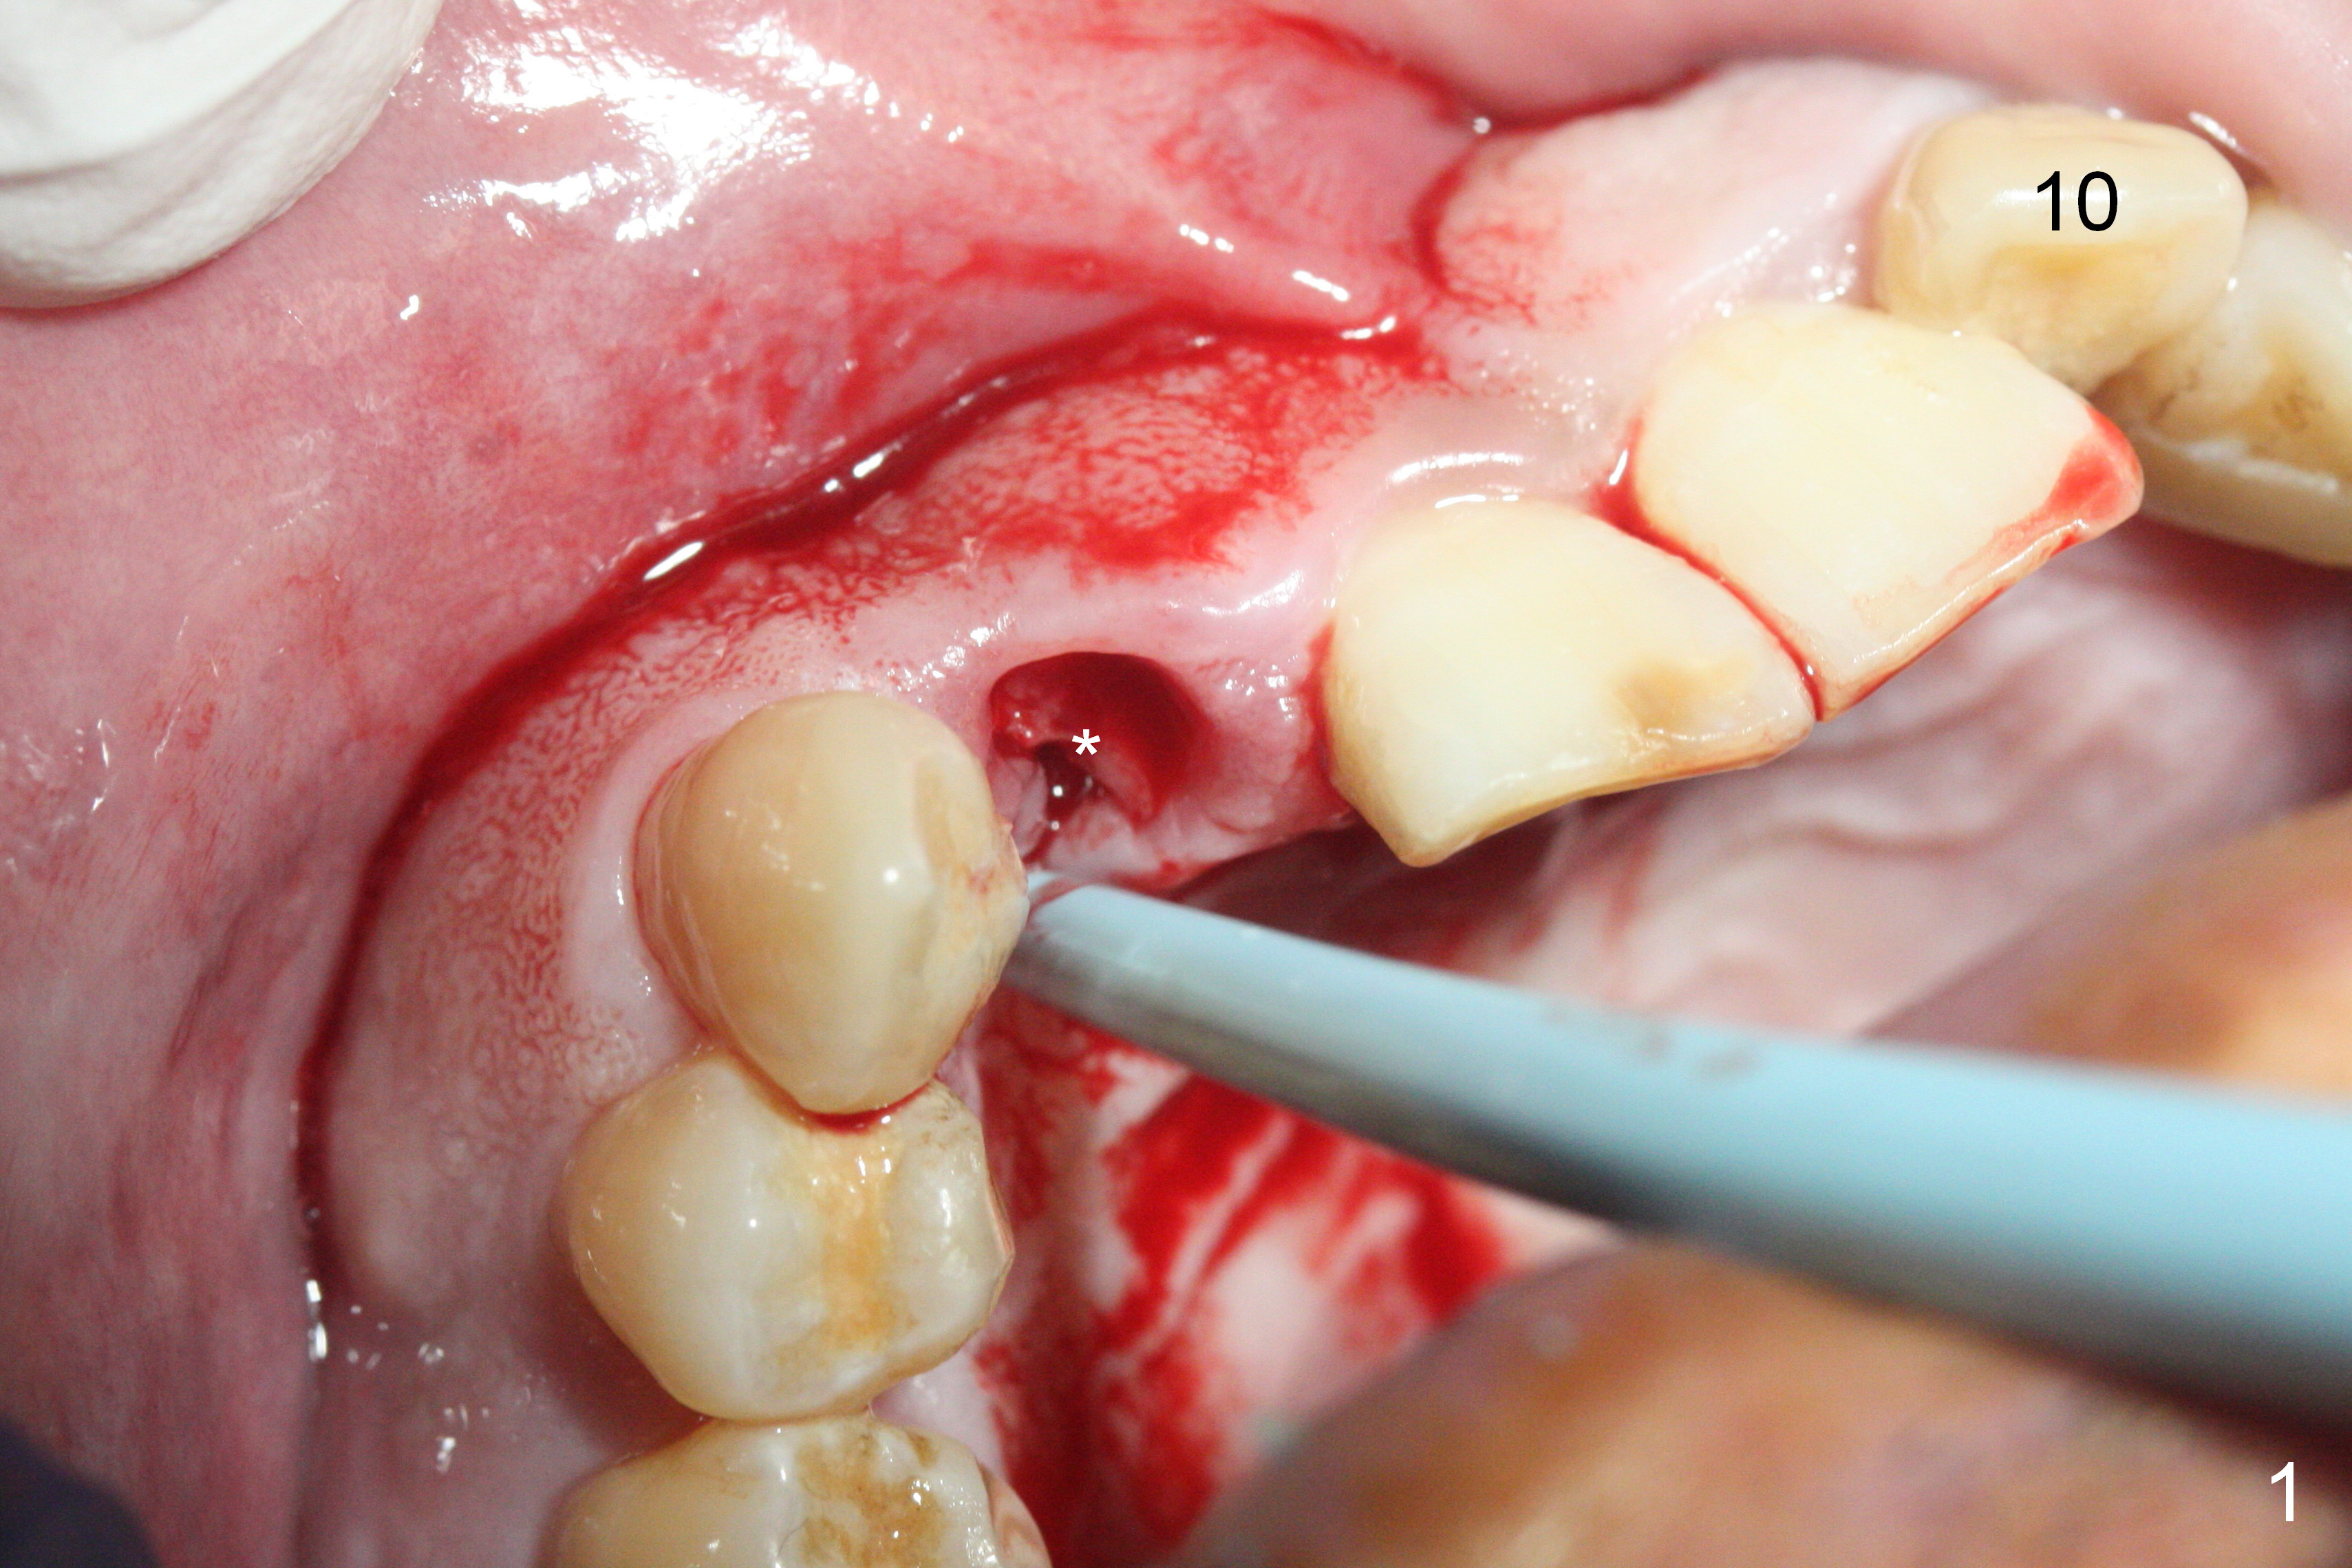

Sixteen days postop, the patient is doing fine, although the labial fistula has not disappeared (Fig.8 <). The detached distolabial papilla is healing (Fig.9 *) with mild bone graft exposure (^). The lacerated distopalatal papilla is also healing (Fig.10 *). These complications are related to flap surgery. The apical portion of the socket appears to have reduced 4 months postop (Fig.14). When the definitive restoration is delivered 5 months postop, there is gingival recession, including the distal of #8 (Fig.11 arrows, which is expected to improve over time) due to flap surgery. The labial plate collapse is minimal (Fig.12 *), while the palatal laceration (Fig.10) has healed (Fig.13). When the patient returns 1.5 years post cementation, there is increased bone density next to the coronal portion of the implant, equivalent to the bone graft (Fig.15 *). The fistula is absent (Fig.16). The crestal bone loss remains 2.5 years post cementation (Fig.17 *), although there is no sign of periimplantitis (magnification). Oral hygiene is poor. There is no change in the soft (gingival recession; data not shown) or hard tissues 3 years 8 months post cementation (Fig.18).